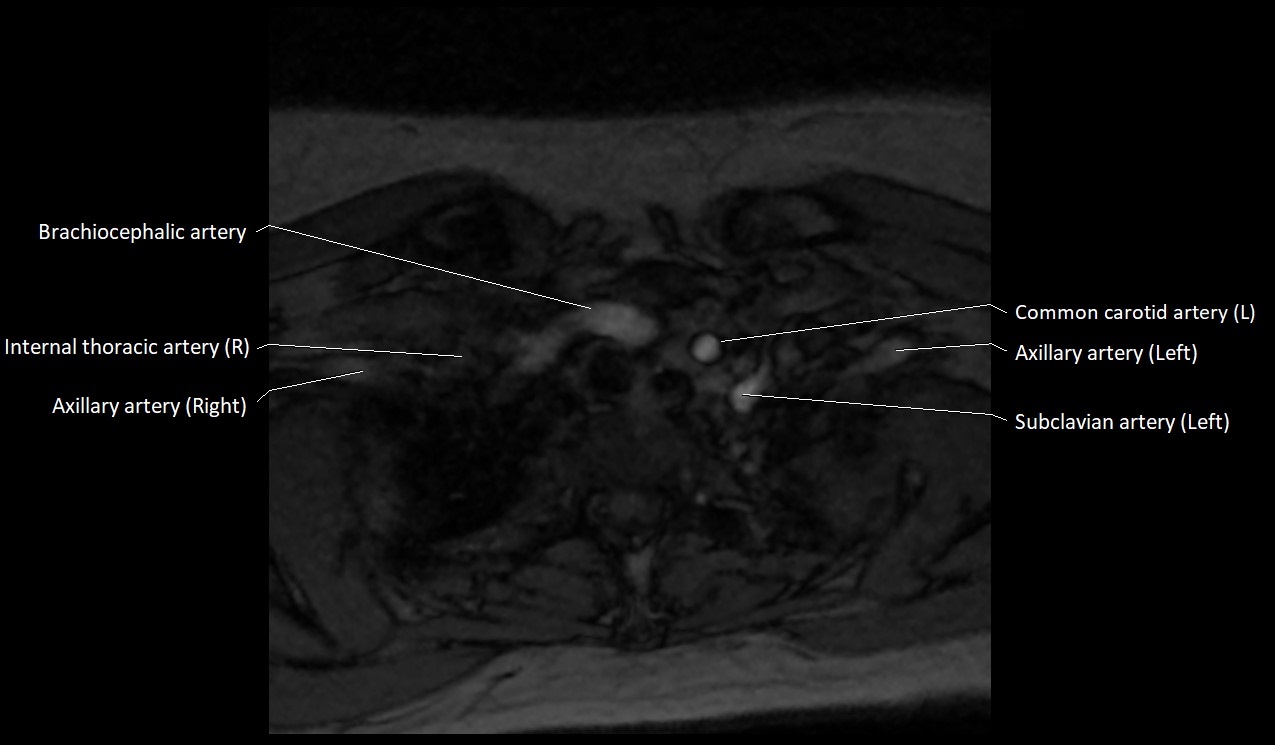

MRI images

image